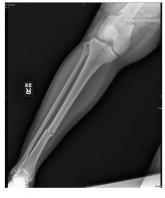

After accidentally being run over by a vehicle, a 54-year-old man presents to the emergency department for evaluation of pain in his elbow and left ar...